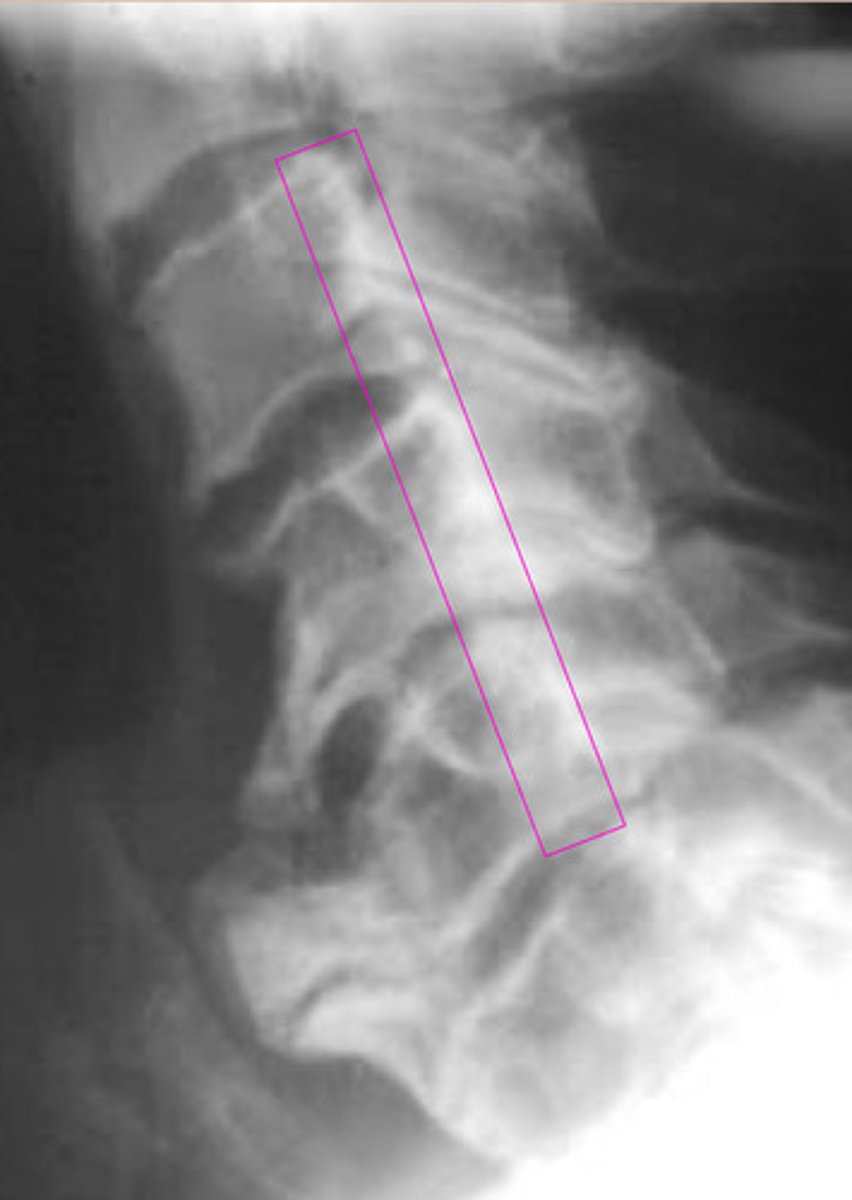

DISH/AH

What is this image showing?

Ossification of the PLL

Laminectomy

What is the pink?

What happened to there spinous processes?

Ossification of PLL

What is the blue?

Can cause cord stenosis

What is so dangerous of OPLL (ossification of PLL)?

AH

OPLL

What is the green?

What will cause the cord herniation